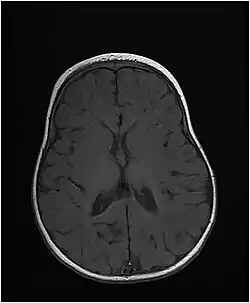

Заболевание начинается с рождения либо в раннем младенческом возрасте, проявляясь такими симптомами, как микроцефалия, низкий рост, задержка психического развития. У пациентов развиваются эпилептические судороги, которые иногда с трудом поддаются контролю. На снимках мозга наблюдается задержка образования миелиновой оболочки либо потеря миелина.